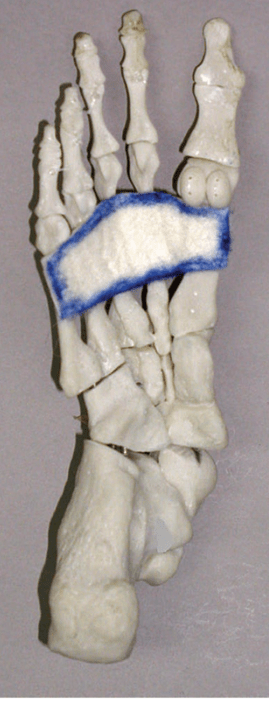

Name this tissue. It supports the arch of the foot, absorbs and redistributes force, and stabilizes the foot during movement. Two words in the name.

Plantar Aponeurosis or Plantar Fascia